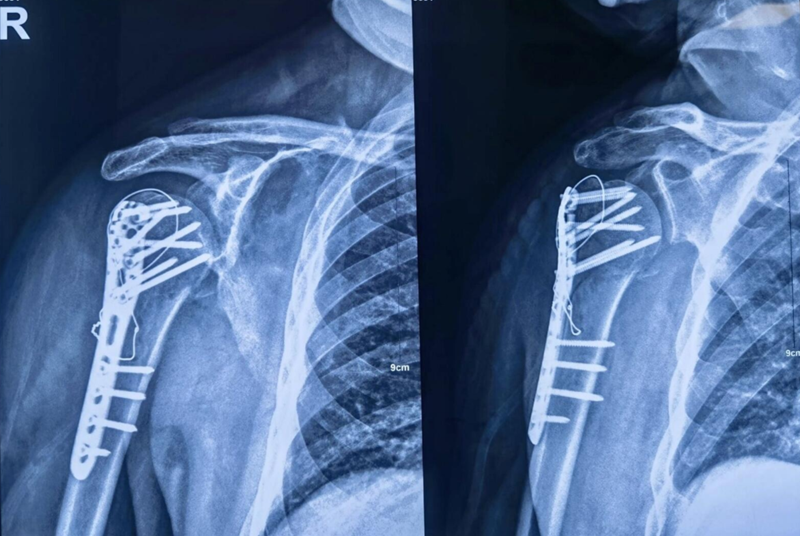

图19 术后X片